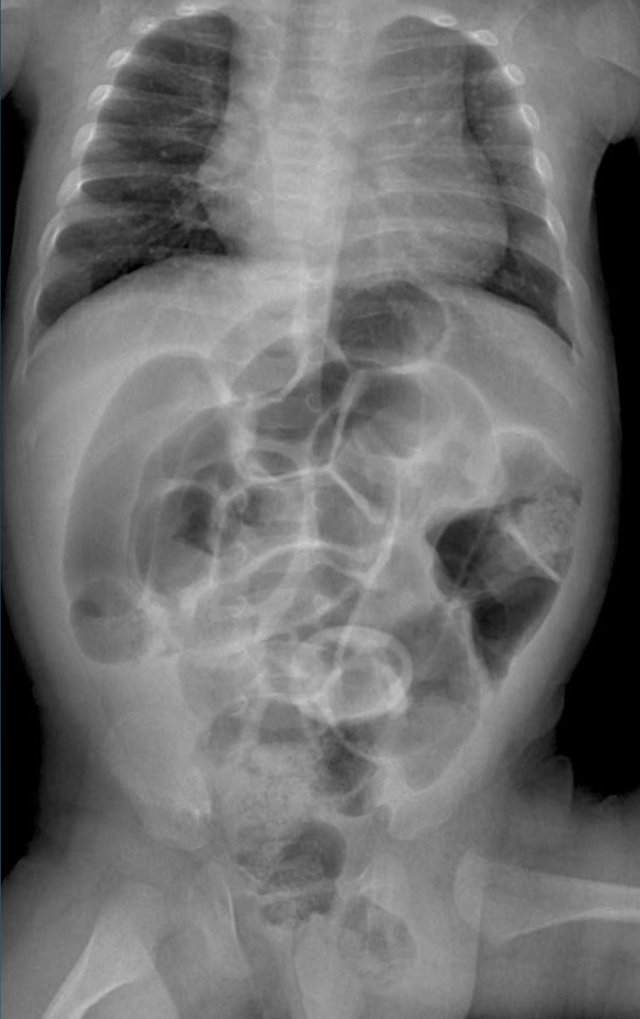

On the left image the bowel is dilated and the diameter exceeds L2 interpedicular width in a patient with meconium ileus.

On the image on the right there is massive dilatation in a neonate with jejunal atresia.